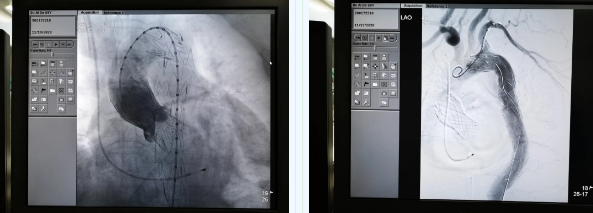

11月19日,西安國際醫(yī)學(xué)中心醫(yī)院心臟外科TAVR團隊在心臟病醫(yī)院張金洲副院長主持下,順利完成一例罕見“經(jīng)股經(jīng)導(dǎo)管主動脈瓣置換術(shù) 經(jīng)導(dǎo)管主動脈腔內(nèi)隔絕術(shù)”。經(jīng)查閱文獻證實,此一站式復(fù)合手術(shù)國內(nèi)尚未見報道。由此,西安國際醫(yī)學(xué)中心醫(yī)院心外團隊在心臟微創(chuàng)治療領(lǐng)域又向前邁進了一大步。

張金洲副院長關(guān)注著手術(shù)的每一個細(xì)節(jié),從建立軌道、跨瓣、釋放瓣膜、支架定位、造影和食道超聲確認(rèn),每一步都緊張而有序地進行著。為了最大程度保障病人安全,心臟外科程亮副主任也帶隊建立動靜脈入路,以備緊急體外循環(huán)。經(jīng)過團隊每一位成員的密切配合,在近四小時的緊張奮戰(zhàn)之后,“TAVR TEVAR”復(fù)合手術(shù)順利完成;經(jīng)過造影和食道超聲證實:人工主動脈瓣無返流無瓣周漏、冠脈顯影良好,主動脈覆膜支架無內(nèi)漏無移位。